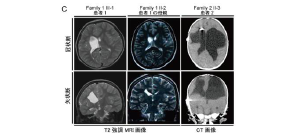

2012.03.03 松本直通教授ら研究グループが重症型もやもや病の遺伝マーカーを発見!